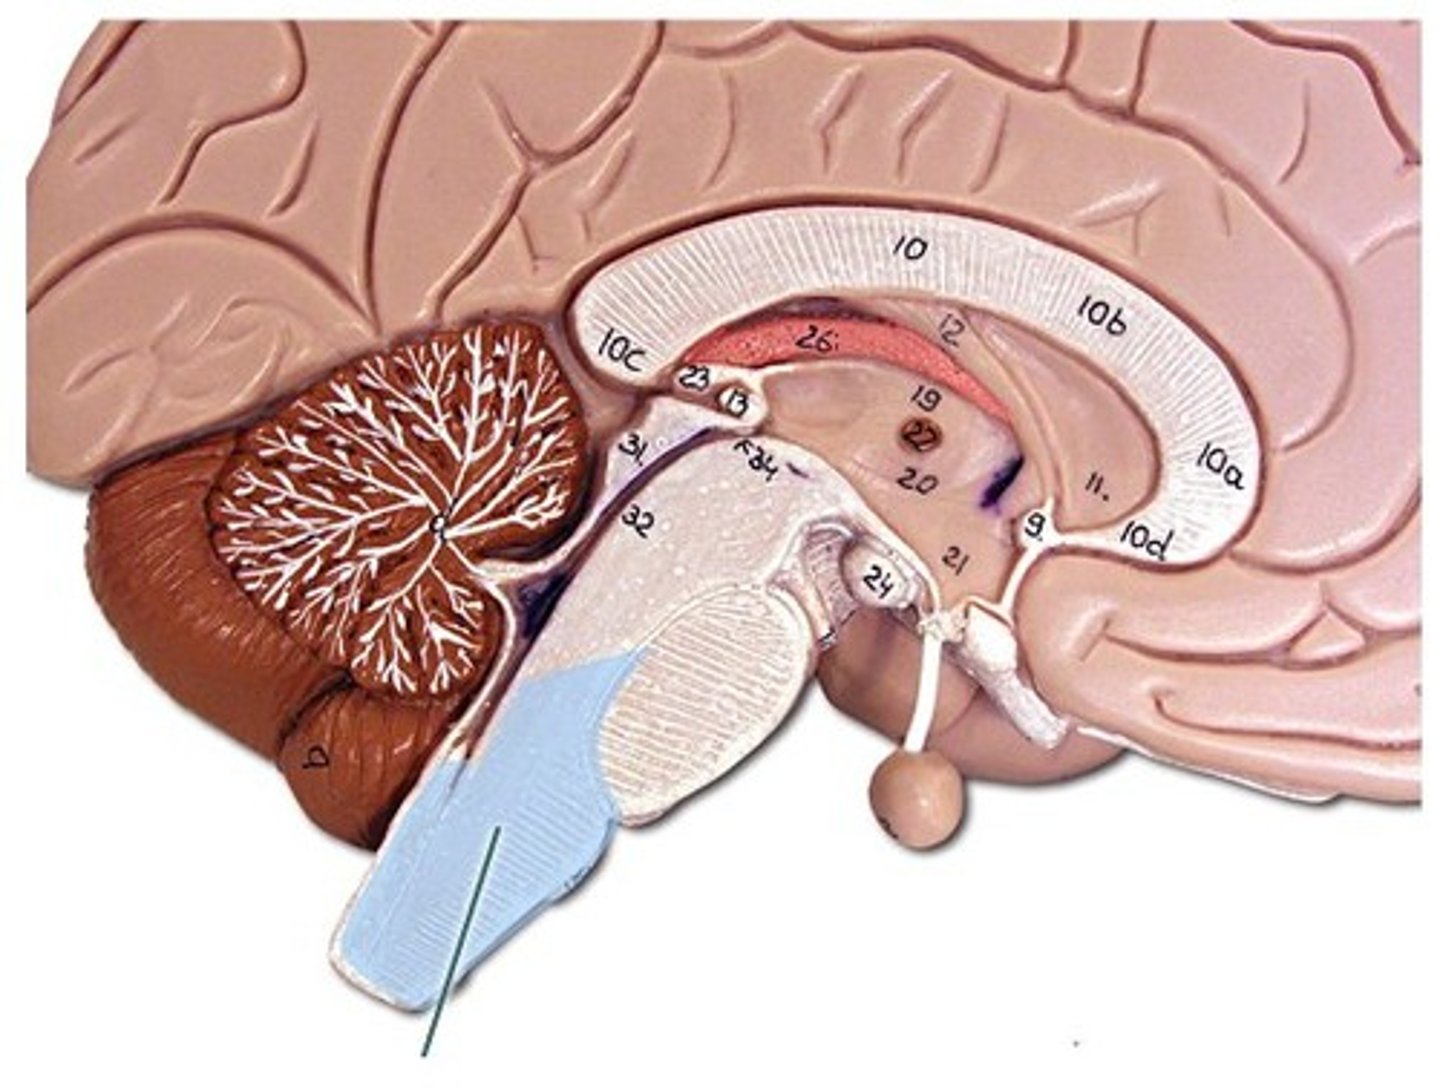

corpus callosum

A thick band of axons that connects the two cerebral hemispheres and acts as a communication link between them.

Diencephalon

central part of the brain made up of the thalamus, hypothalamus, and epithalamus

thalamus

hypothalamus

pituitary gland

midbrain (mesencephalon)

pons

medulla oblongata

cerebellum

arbor vitae